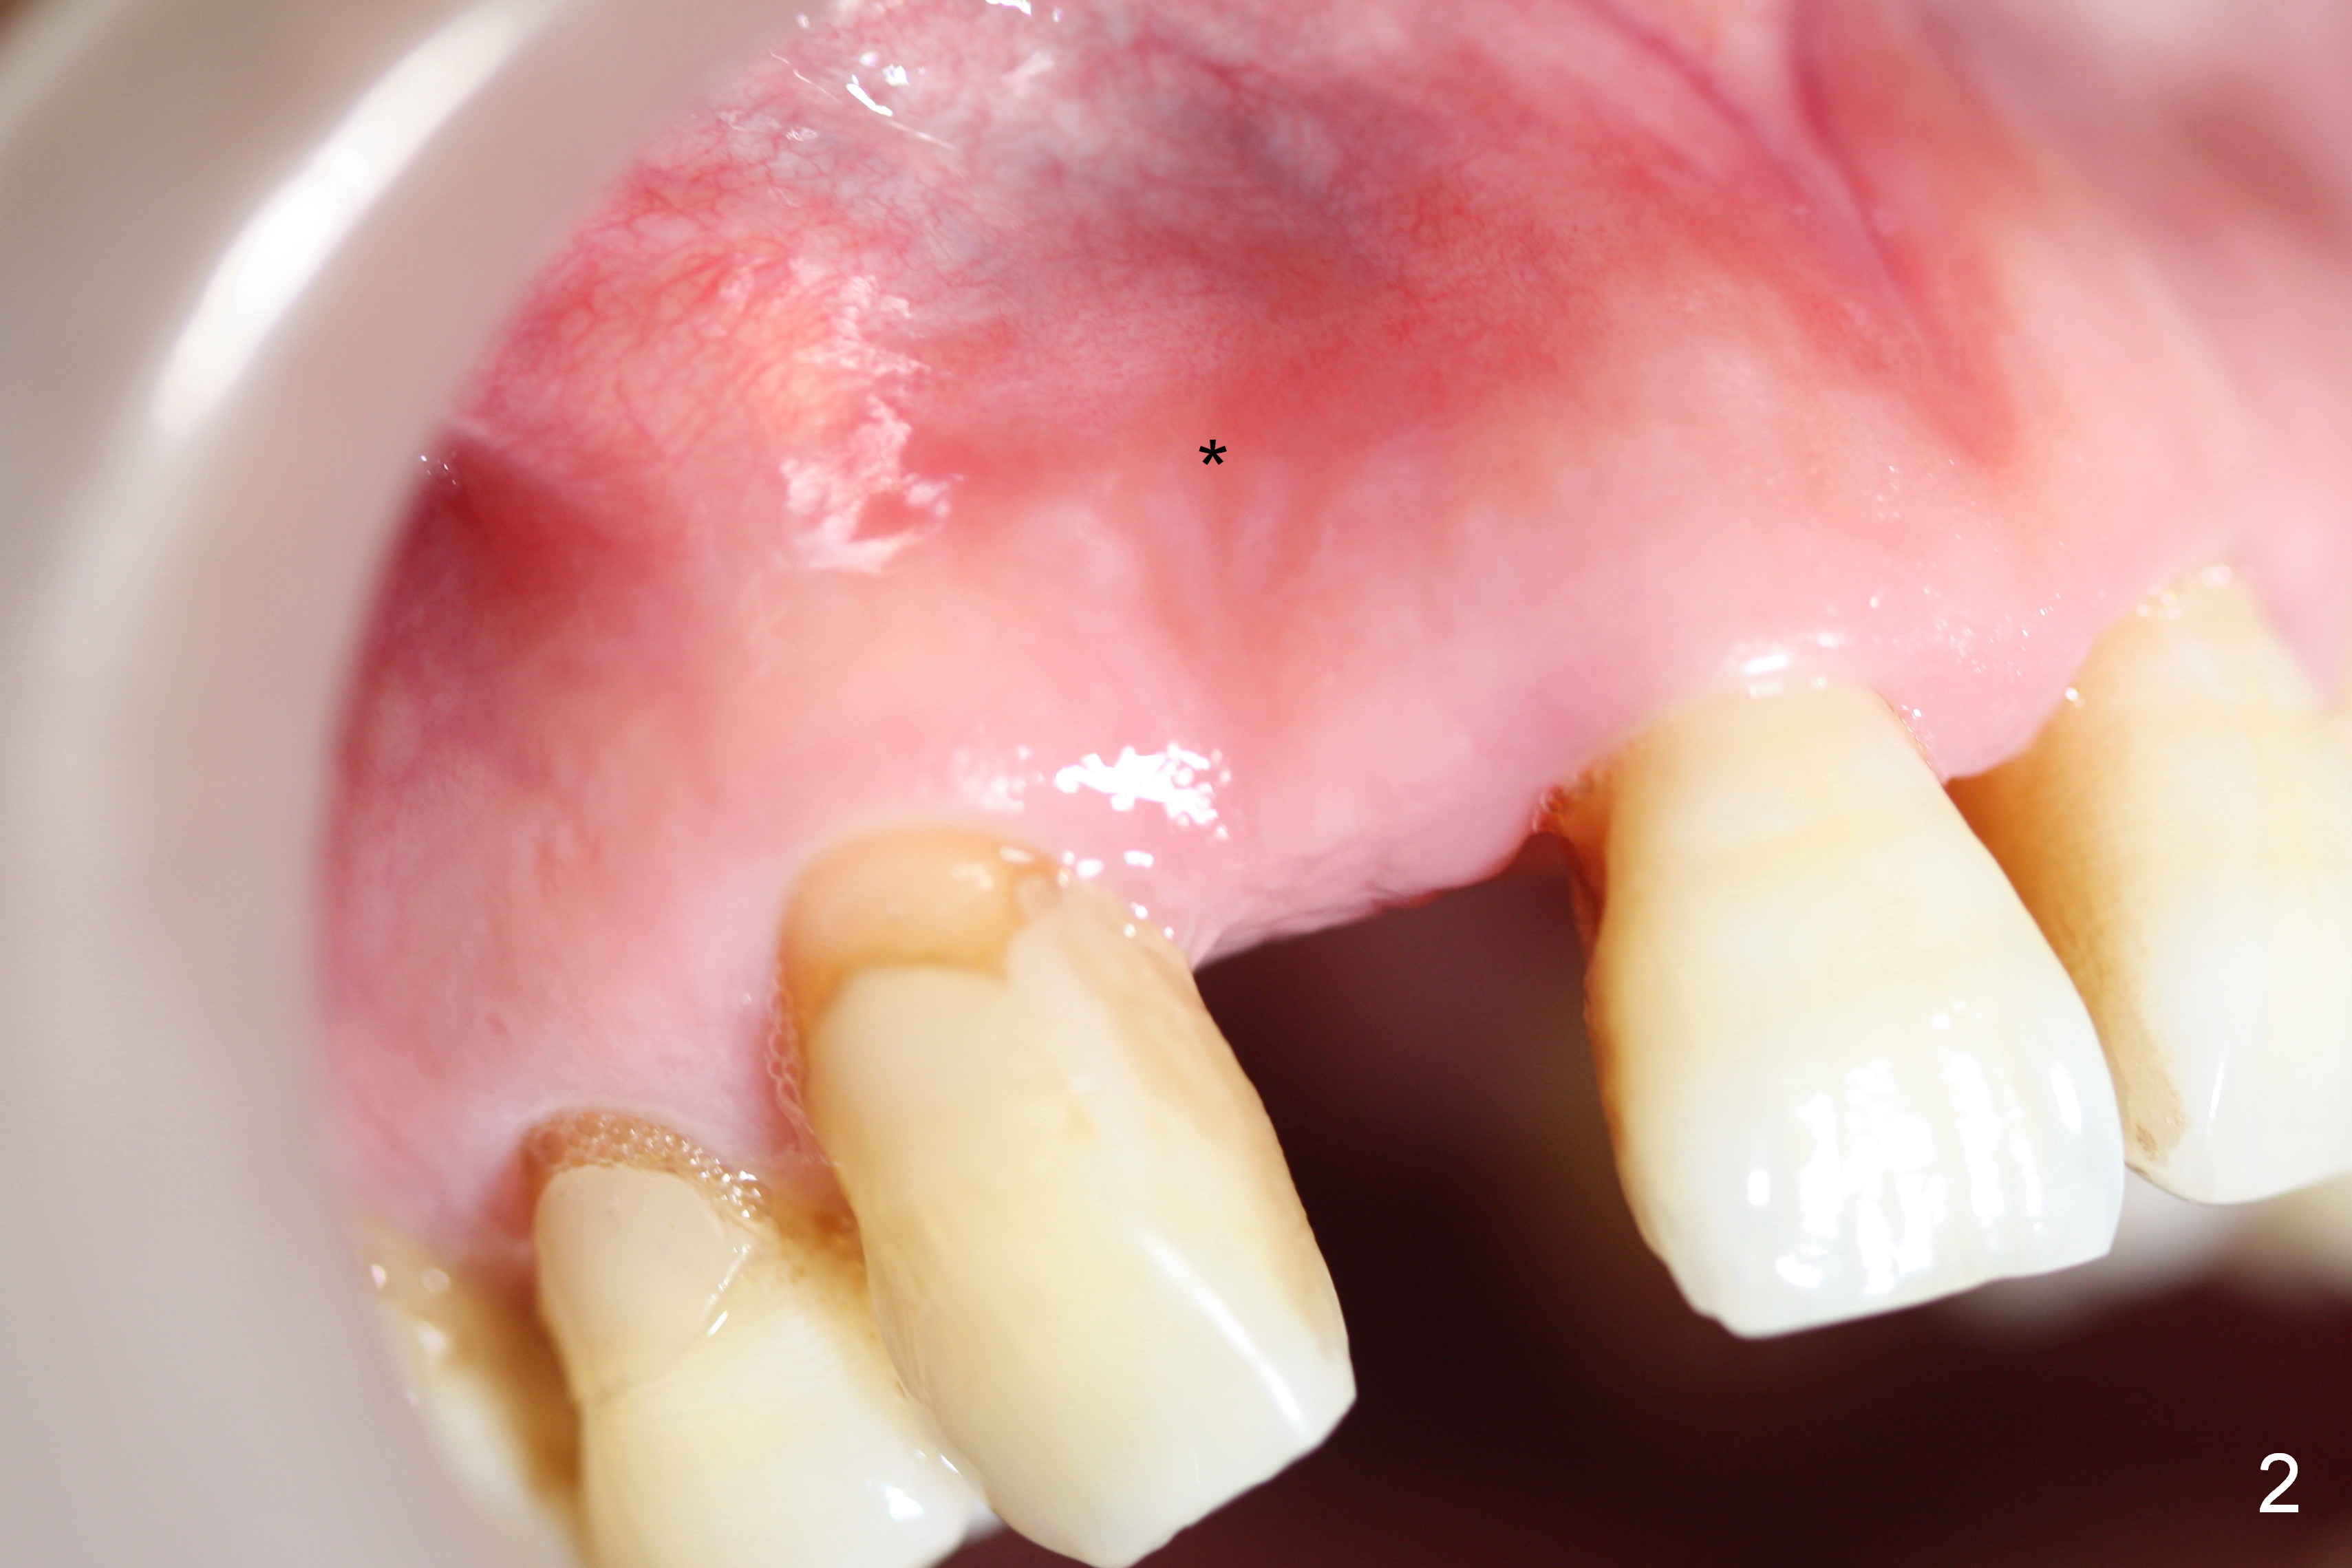

Preop exam shows the apparent wide ridge at #7 (Fig.1). What is ignored preop is the concavity in the apical buccal region (Fig.2 *). When a 3x16(4) mm 1-piece implant is being placed (Fig.3 *, flapless), the apical buccal plate vibration is felt. The biggest mistake is that initial osteotomy is ~ 6 mm shy of the implant length, partially because of 6 mm gingival height. Since the tooth #6 is symptomatic after RCT with paste overfill (Fig.4 >), apicoectomy is contemplated at #6 with exploration of the buccal plate at #7 (Fig.5). Since the implant appears to be long enough, implant apical resection is performed (Fig.6). Since there is coronal thread exposure due to previous periodontitis (Fig.7 <), bone graft is placed in these 3 defective areas after decortication.